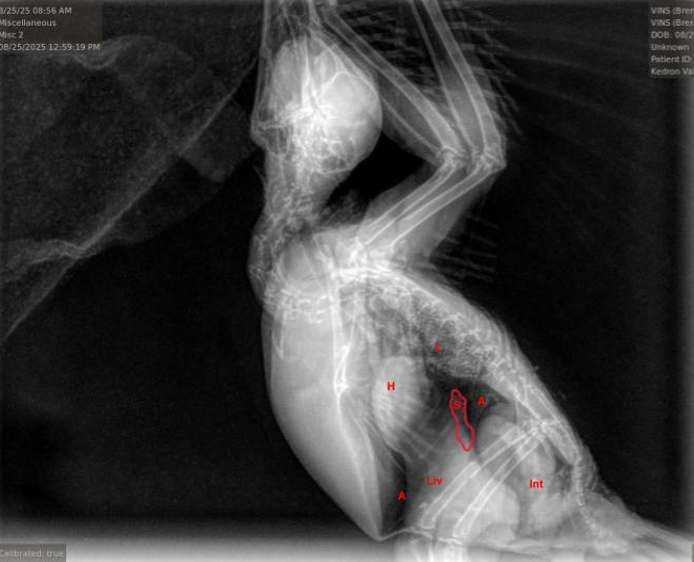

Rehab Fact: Avian Malaria

When you think of malaria, you probably think of the tropics – after all, that’s where humans can be infected. For birds though, malaria is worldwide, present on every continent except Antarctica (at least for now). Birds across the world have evolved with dozens of malaria species, and most of the time are only subtly affected. However, changing infection and environmental dynamics have altered this balance, sometimes in dramatic ways. Invasive malaria has caused the extinction of about a third of Hawaii’s honeycreeper species since the late 1800’s, and other introduced strains, global warming and environmental toxins have made malaria infections more dangerous over time. But before we get into how it affects Vermont’s birds, what exactly is malaria?

Malaria is caused by a single celled parasite in the genus Plasmodium, that has a complex life cycle involving both mosquitoes and vertebrate hosts. Briefly, an infected mosquito bites a bird, human, or other animal, and the parasites are transmitted in the saliva. They initially undergo asexual reproduction in tissue cells, then invade red blood cells. Once the blood is infected, gametes, the mature parasites, can be taken up by a mosquito to continue the infection cycle. A second form, called schizonts, develop into clusters of smaller forms called sporozoites, and when the schizont is mature it ruptures the red blood cell, allowing the sporozoites to spread and infect other red blood cells. Destruction of red blood cells leads to anemia, which can cause weakness, circulatory disorders and kidney damage. The red blood cell turnover also leads to a greatly enlarged liver and spleen, which can put pressure on the air sacs and contribute to respiratory difficulty. Somewhat unique to birds, tissue stages can also cause severe disease or death, particularly when the cells that line blood vessels become infected and swollen, which can lead to blockages that prevent blood flow to parts of the brain. Finally, immune compromise from malaria infection can lead to high rates (>40%) of severe bacterial and fungal coinfections, making treatment substantially more difficult.

So what birds in Vermont are affected by malaria? It was first discovered in Northeastern common loons in 2017, and has caused mortalities each year, making it an emerging disease, although luckily it hasn’t seemed to cause major impacts so far. The more widespread effect is in passerines, which is where nearly all cases have been seen in CWBR. It is primarily a disease of juvenile birds, particularly American robins, corvids and grackles. In fact, in some years it is a leading cause of infectious disease deaths in robins, with 7 cases and 5 deaths in 2025- making it responsible for 25% of deaths in care for robins this year. I suspect that it is an underrecognized disease in juvenile passerines, for a variety of reasons: many rehabilitators either don’t or can’t do bloodwork on songbirds, or don’t perform necropsies regularly. Additionally, many field studies on malaria focus on breeding or migrating adults, and don’t focus on the population most vulnerable to infectious diseases- young birds. This has been an area of ongoing research for me, to better understand pathology in wild birds, improve ability to detect and identify coinfections, use these findings to guide treatments and ultimately to publish these findings and increase awareness about this significant disease of wild and rehabilitated birds.